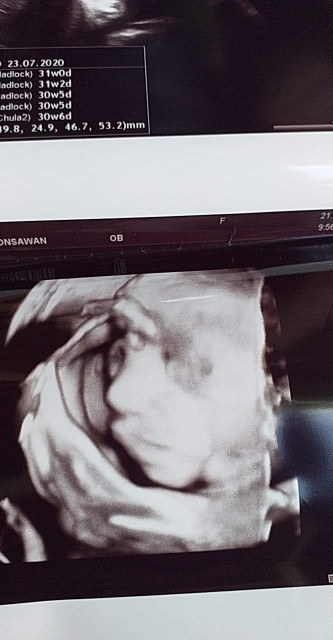

ผู้ชายคัฟ ซาว์เมื้อวาน30w